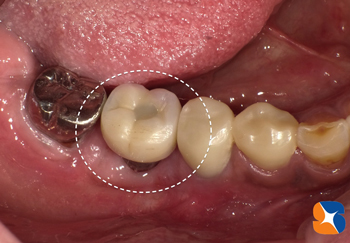

50代の女性。大阪市内よりセカンドオピニオンとして来院。相談は「歯周病が原因で歯を抜いた。患部に『1回の手術で噛めるインプラント』をすすめられている。大丈夫でしょうか?」

Dr「手術予定部の歯肉は貧弱なため、完成したインプラントを磨くにはとても不利な歯茎です。抜歯された歯と同じく、インプラント周病になる可能性があります。『一生涯持たせたい』とお考えなら『急がば回れ』です。